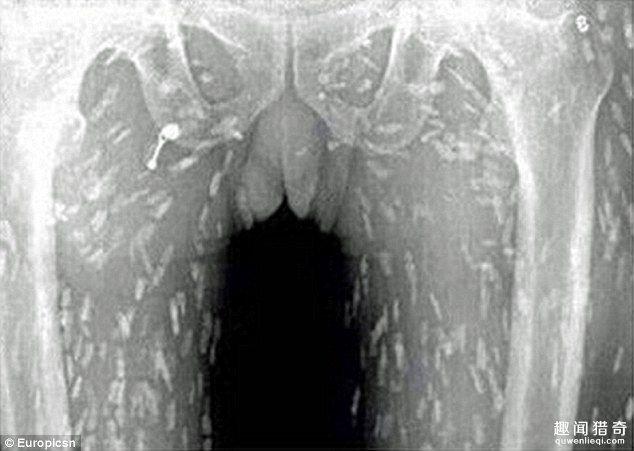

相信不少人都非常喜歡吃生魚片,近日,一名男子卻因為過度食用生魚片而差點喪命。 據報道,這名男子因為腹痛和皮膚瘙癢而前去醫院就診,在X光下顯示了這駭人的一幕。

這名男子的身上已經全是寄生蟲,看了讓人頭皮發麻。 醫生認為他是因為吃了太多的生魚片,才會有如此嚴重的感染。 目前他正轉往廣州市第八人民醫院接受治療。